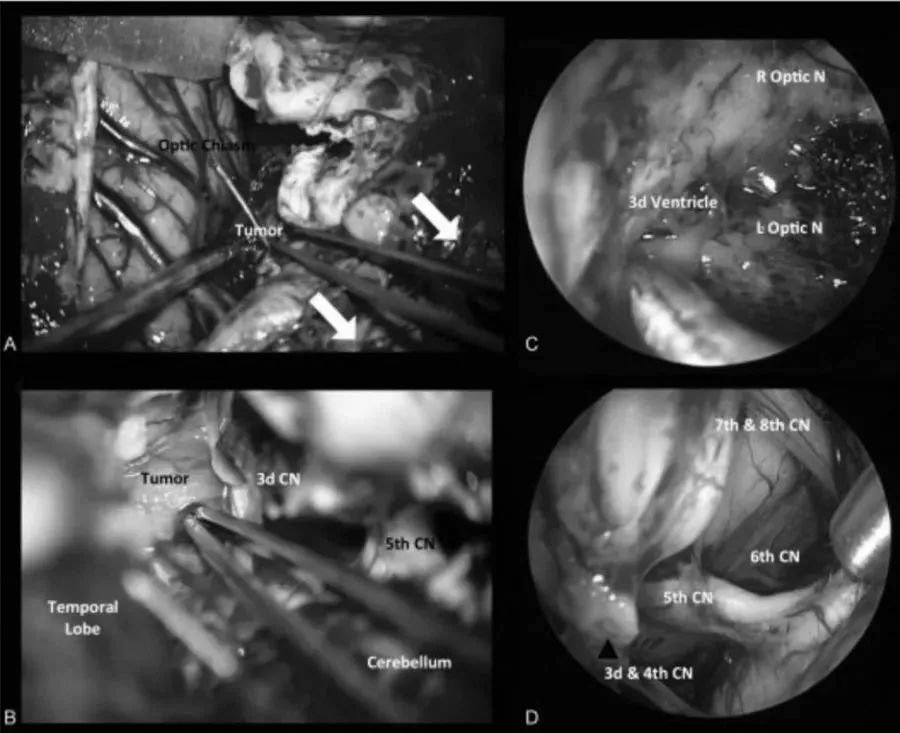

術(shù)中圖像:(A)在經(jīng)后巖骨入路時(shí),橫竇-乙狀竇連接處的后部移位,為顳葉與后顱窩之間的手術(shù)通道(白色箭頭)。(B)腳間池蛛網(wǎng)膜的初步解剖分離,腫瘤的暴露。內(nèi)窺鏡輔助可以對(duì)手術(shù)床進(jìn)行詳細(xì)檢查(C),以便更好地了解周圍的神經(jīng)血管解剖結(jié)構(gòu)(D)。CN,顱神經(jīng);L視神經(jīng)N,左視神經(jīng);R視神經(jīng)N,右視神經(jīng)。

圖2術(shù)中圖像:(A)在經(jīng)后巖骨入路時(shí),橫竇-乙狀竇連接處的后部移位,為顳葉與后顱窩之間的手術(shù)通道(白色箭頭)。(B)腳間池蛛網(wǎng)膜的初步解剖分離,腫瘤的暴露。內(nèi)窺鏡輔助可以對(duì)手術(shù)床進(jìn)行詳細(xì)檢查(C),以便更好地了解周圍的神經(jīng)血管解剖結(jié)構(gòu)(D)。CN,顱神經(jīng);L視神經(jīng)N,左視神經(jīng);R視神經(jīng)N,右視神經(jīng)。